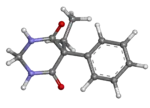

| 3D model (JSmol) | |